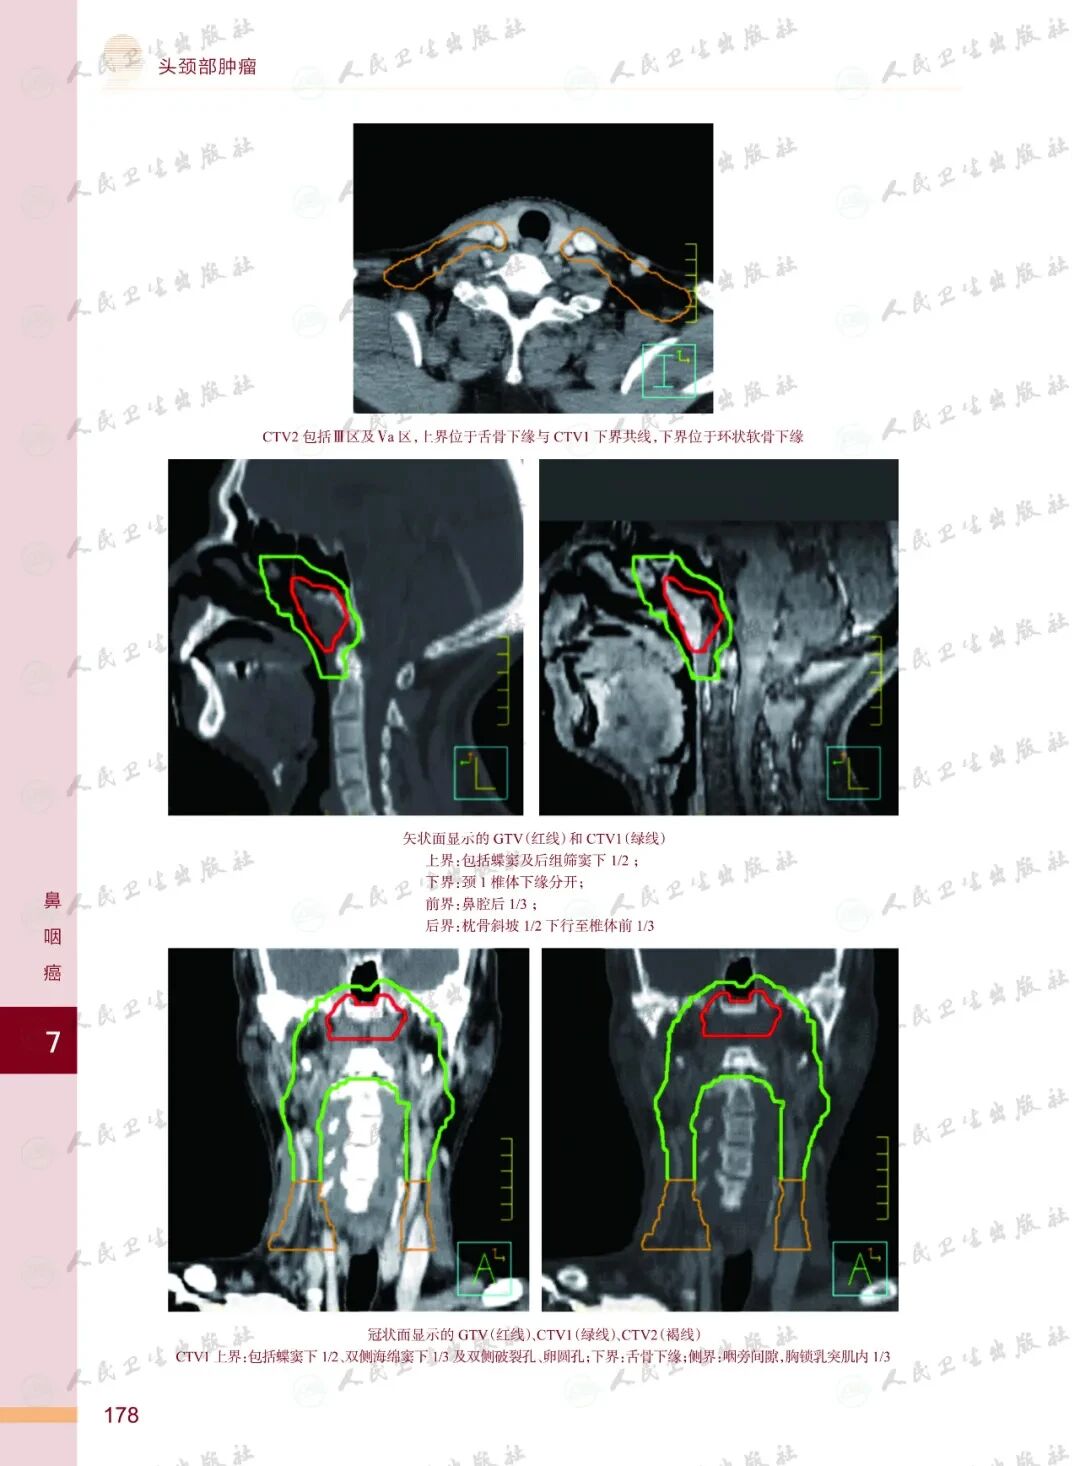

《头颈部肿瘤放射治疗图谱》

——不止是图谱,更是随唤随应的临床良师

样章试读